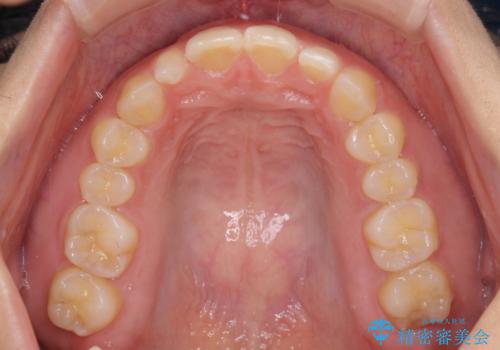

- 前歯の空隙と矮小歯を気にして来院された患者様です。

上下の歯列不正はインビザラインにより整えることとしました。

矯正治療の後に、前歯1歯と奥歯をオールセラミックにて治療することとしました。

矯正治療により矮小歯前後にスペースを作りながら歯列を整え、セラミッククラウン装着後に最終的に歯列と咬合を仕上げました。